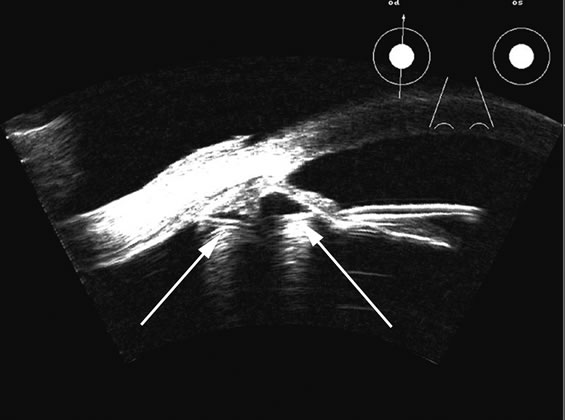

Fig. 7. This B-scan ultrasonogram demonstrates retinitis proliferans with typical vitreous membrane attaching to the proliferative membrane (arrows) that can resemble a traction detachment. Scanning at right angles helps distinguish proliferative membranes from retinal traction membranes, as they have less reflectivity than retina.

Fresh blood in the vitreous may be acoustically clear since the red cells may not have congealed sufficiently to form a good echo-producing surface.8 A retracted “hyaloid” or posterior limiting membrane (PLM) of the vitreous can be shown with most B-scan instruments, but paradoxically a retracted vitreous may not be seen as well with higher-resolution, more highly focused transducers because they display less area of the reflective surface. Blood collected on the surface of the PLM enhances this surface and may, in some cases, make the PLM resemble a detached retina, since its anatomic dimensions can be similar to the retina. Three differences may help distinguish the two structures. First, kinetic scanning reveals a lack of attachment at the optic nerve for a PLM. Second, the PLM is irregular in reflection and thickness (usually thicker than the retina) between the ora and the disc, and usually the surface cannot be traced forward to the ora on the B-scan display. Third, the amplitude of the echoes from the PLM is lower than from the retina, except when directly perpendicular to the beam, where they may be similar in amplitude. Many of these features of a PLM are demonstrated in Figure 7, whereas Figure 8 shows a typical detached retina.